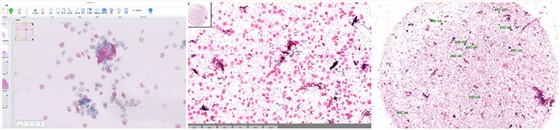

AI判读:

基于AI的超分辨成像+智能判读

针对乳腺癌、宫颈癌、结直肠癌、白血病开发独立的人工智能诊断模块,单视野的敏感性和特异性都超过97%,整张玻片的敏感性低度病变及高度病变类型病例的检出率超过96%